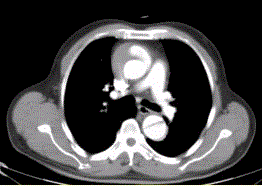

问题 患者男,67岁,高血压病史多年,自服降压药,突发胸骨后剧烈疼痛2h,服用硝酸甘油不缓解。胸透示主动脉增宽。CT影像如下图。 该病例的诊断为

选项 A.主动脉夹层 B.主动脉瘤 C.主动脉破裂 D.主动脉假性动脉瘤 E.主动脉血栓再通 F.大动脉炎

答案 A

解析 A